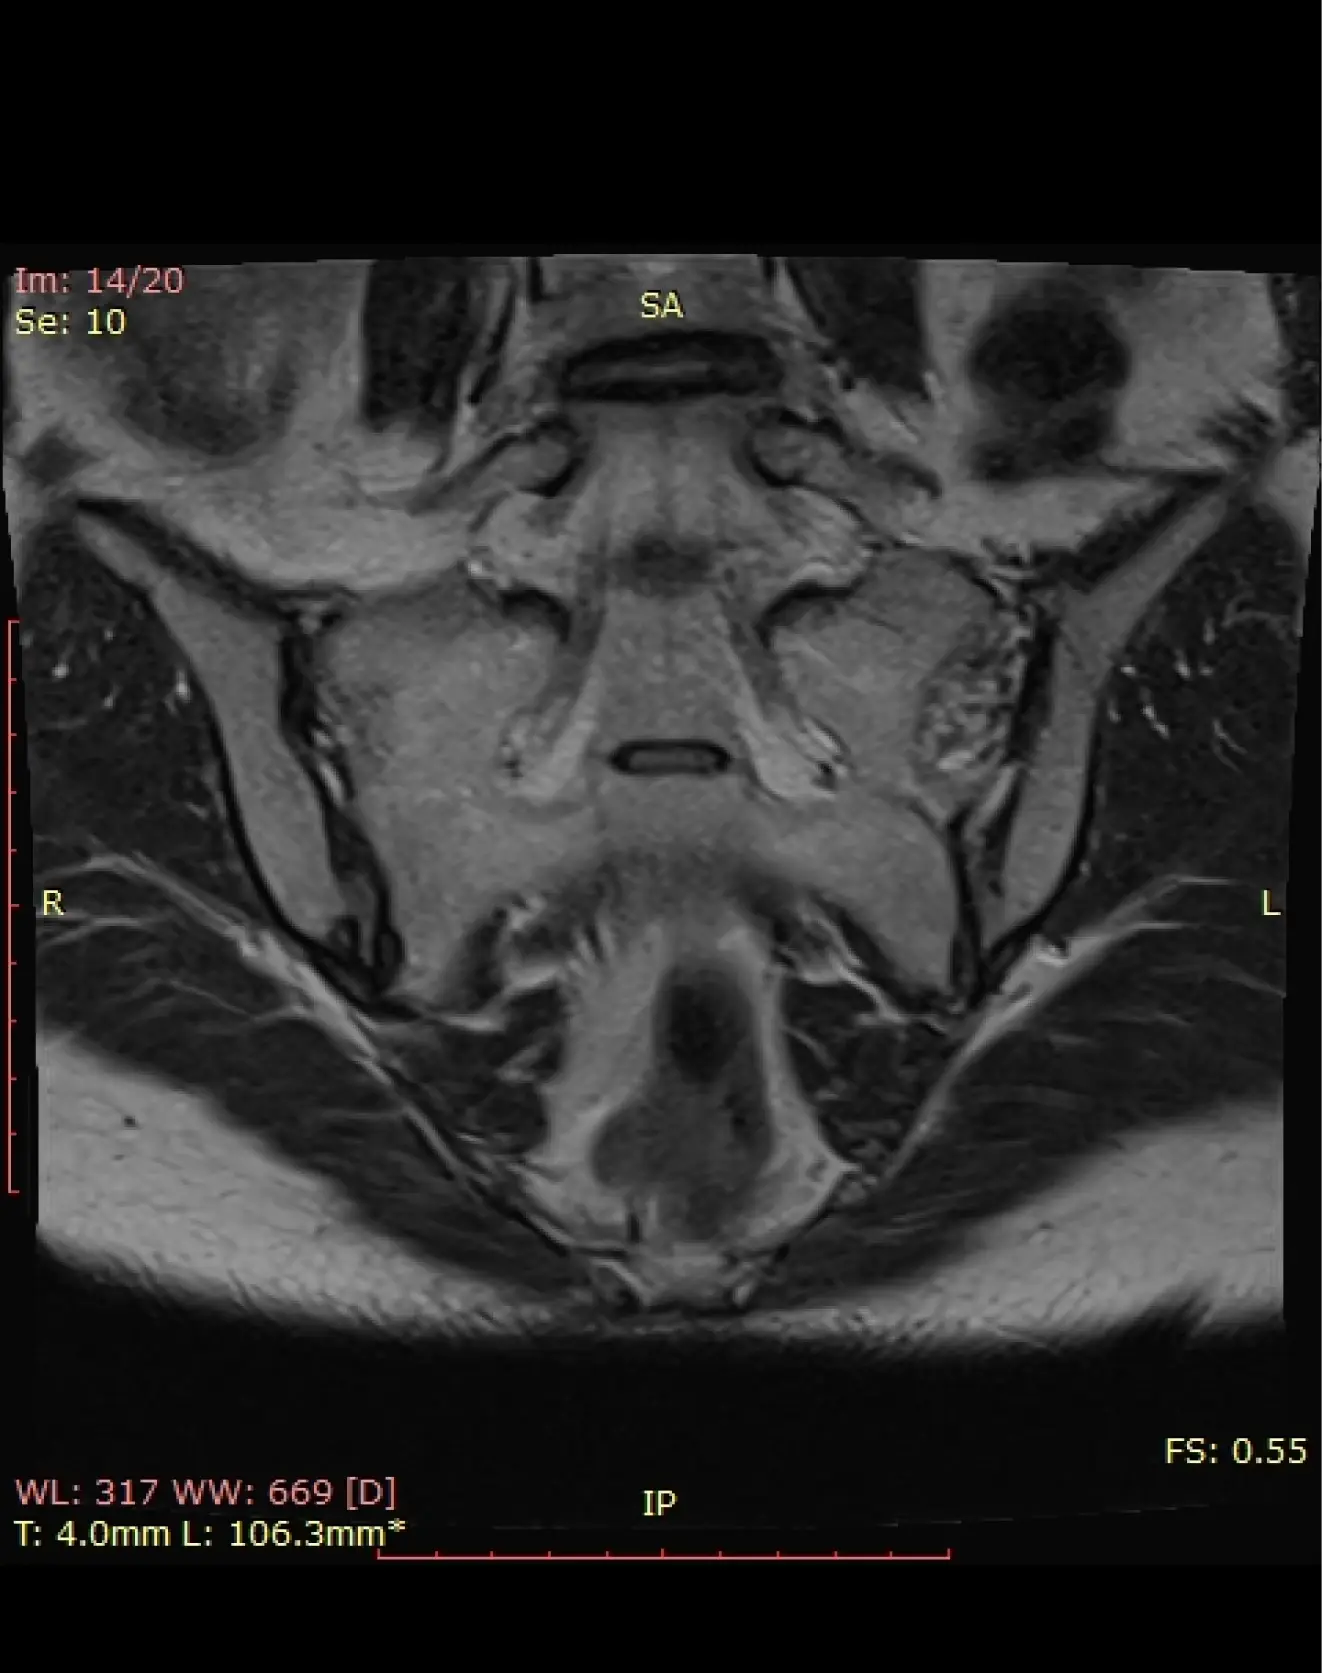

Подготовка к МРТ малого таза (женщины)

• Исследование проводится на 7–12 день менструального цикла.

• Возможно проведение во вторую фазу цикла по рекомендации врача.

• После диагностического выскабливания (полости матки, цервикального канала) – не

ранее чем через 1,5 месяца или по согласованию с врачом.

• В меру полный мочевой пузырь, так же необходимо почистить кишечник перед МРТ.